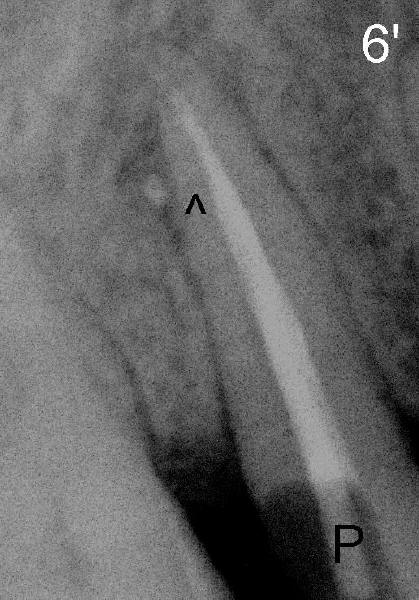

The lateral canal appears to be filled (Fig.6 arrowhead).  It is also shown during prefabricated post placement (Fig.6 P: post).  Return to the main text